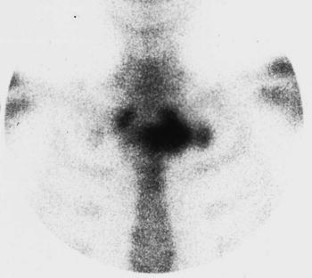

The SAPHO syndrome was a term coined to include a variety of musculoskeletal disorders associated with skin conditions, mainly palmoplantar pustulosis and acne conglobata. It is more correctly a spectrum which includes the following: skin lesions, osteoarticular manifestations of synovitis hyperostosis and osteitis affecting particular target sites, and·a clinical course marked by relapses and remissions. The major sites of involvement are the anterior chest wall, the spine, long bones, flat bones, and large and small joints. The distribution and severity of involvement varies from the adult to the pediatric form of chronic recurrent multifocal osteomyelitis (CRMO). The diagnosis of SAPHO syndrome is not difficult when the typical osteoarticular lesions are located in characteristic target sites. The diagnosis is more difficult if atypical sites are involved and there is no skin disease.